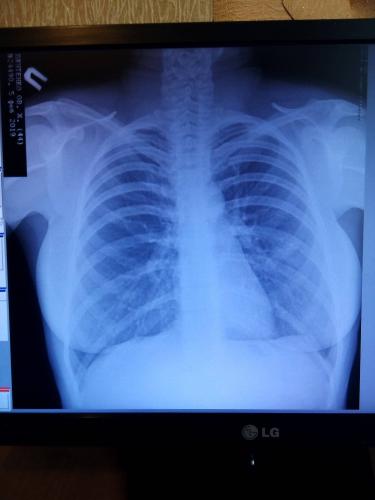

Помимо внешнего осмотра, сбора анамнеза, в том числе жалоб пациента, рентгенологического исследования легких, общего и клинического анализа крови, особое значение для подбора эффективной терапии имеют исследования, связанные с определением возбудителя болезни.

Почему после пневмонии держится температура 37°С? Обычно температура после прохождения полного курса лечения — это вполне нормально явление, если клинический анализ крови и показатели рентгена легких в норме.

Сначала врач ознакомится с жалобами больного, проведет осмотр пациента, оценит состояние его носоглотки. В обязательном порядке требуется проведение флюорографии. Пациенту необходимо сдать кровь и мочу на анализы. Кроме того, исследуется мокрота больного на микрофлору, что дает возможность определить ее характер. Ну и, конечно, следует проверить температурные показатели пациента. После того как будут получены результаты исследований, можно получить полную картину болезни и подобрать действенный способ лечения.